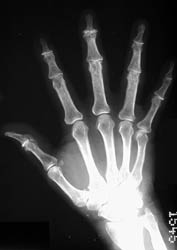

Primary osteoarthritis of the hands typically targets the PIP, DIP,

scaphotrapeziotrapezoid and the 1st carpometacarpal joints. The knee, hip,

spinal, and 1st metatarsophalangeal joints are other areas which are commonly

involved. Additional joints can be affected in cases of secondary osteoarthritis.

Radiographic Findings: Affected joint spaces are narrowed with reactive

subchondral sclerosis (eburnation). Other classic radiographic findings include

osteophytes and subchondral cysts. Heberden's nodes at the DIP joints and

Bouchard's nodes at the PIP joints of the hands are areas of osteophyte formation

and soft tissue swelling associated with osteoarthritis. Intraarticular loose